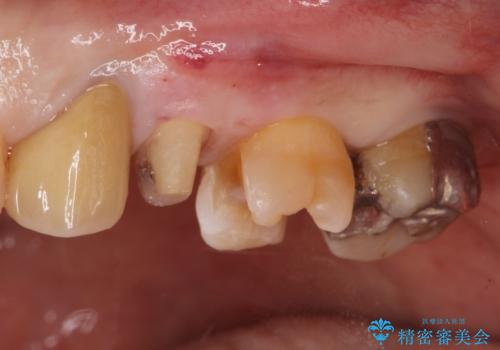

左上の歯が欠けた。

- 左上の歯が欠けたとの事で来院。

銀歯を除去し隣の歯も虫歯が見られたのでジルコニアクラウン、e-maxインレーで治療を行いました。